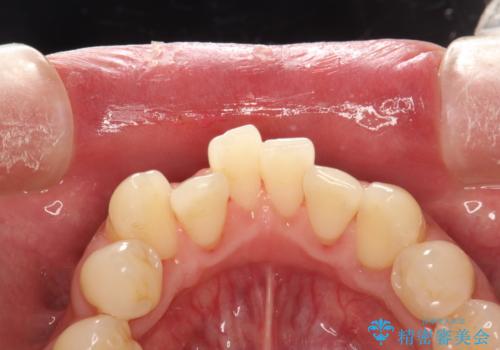

- 治療計画

- 歯科でのクリーニングがかなり久しぶりで口臭も気になるとのことで来院されました。PMTCの60分コースで、染め出し・ブラッシング指導・クリーニングを行いました。

適切な歯磨き方法を習得するには、染め出しを行い、磨き残しを把握していくことがポイントです。

磨けているよう、磨いているつもりでも、汚れが残ってしまうと、毎日の歯磨き時間が無駄になってしまうこともあります。効率的に歯磨きを行い、磨き残しを減らせるように、歯科衛生士による専門的な指導を行います。